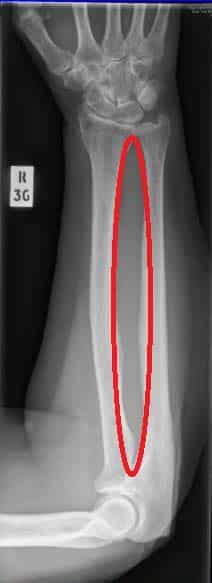

The radioulnar joints are two locations in which the radius and ulna articulate in the forearm: Proximal radioulnar joint – located near the elbow. It is articulation between the head of the radius and the radial notch of the ulna. Distal radioulnar joint – located near the wrist. It is an articulation between the ulnar notch of the radius and the ulnar head. Both of these joints are classified as pivot joints, responsible for pronation and supination of the forearm. In this article, we shall look the anatomy and clinical correlations of these joints. By TeachMeSeries Ltd (2025) Fig 1The proximal radioulnar joint, with the annular ligament. Pro Feature - 3D Model You've Discovered a Pro Feature Access our 3D Model Library Explore, cut, dissect, annotate and manipulate our 3D models to visualise anatomy in a dynamic, interactive way. Learn More Proximal Radioulnar Joint The proximal radioulnar joint is located immediately distal to the elbow joint, and is enclosed with in the same articular capsule. It is formed by an articulation between the head of the radius and the radial notch of the ulna. The radial head is held in place by the annular radial ligament, which forms a ‘collar’ around the joint. The annular radial ligament is lined with a synovial membrane, reducing friction during movement. Movement is produced by the head of the radius rotating within the annular ligament. There are two movements possible at this joint; pronation and supination. Pronation – produced by the pronator quadratus and pronator teres. Supination – produced by the supinator and biceps brachii. By TeachMeSeries Ltd (2025) Fig 2Articulating surfaces of the proximal radioulnar joint. Distal Radioulnar Joint This distal radioulnar joint is located just proximally to the wrist joint. It is an articulation between the ulnar notch of the radius, and the ulnar head. In addition to anterior and posterior ligaments strengthening the joint, there is also a fibrocartilaginous ligament present, called the articular disk. It serves two functions: Binds the radius and ulna together, and holds them together during movement at the joint. Separates the distal radioulnar joint from the wrist joint. Like the proximal radioulnar joint, this is a pivot joint, allowing for pronation and supination. The ulnar notch of the radius slides anteriorly over the head of the ulnar during such movements. Pronation – produced by the pronator quadratus and pronator teres. Supination – produced by the supinator and biceps brachii. By TeachMeSeries Ltd (2025) Fig 3Articular surfaces of the distal radioulnar and wrist joints. Interosseous Membrane The interosseous membrane is a sheet of connective tissue that joins the radius and ulna together between the radioulnar joints. It spans the distance between the medial radial border, and the lateral ulnar border. There are small holes in the sheet, as a conduit for the forearm vasculature. This connective tissue sheet has three major functions: Holds the radius and ulna together during pronation and supination of the forearm, providing addition stability. Acts as a site of attachment for muscles in the anterior and posterior compartments of the forearm. Transfers forces from the radius to the ulna. Clinical Relevance Fractures to the Radius and Ulna Although the radius and ulnar are two distinct and separate bones, when dealing with injuries to the forearm, they can be thought of as a ring. A ring, when broken, usually breaks in two places. The best way of illustrating with is with a polo mint – it is very difficult to break one side without breaking the other. This means that a fracture to the radius or the ulna usually causes a fracture or dislocation of the other bone. There are two classical fractures: Monteggia fracture – fracture of the proximal ulna AND dislocation of the radial head at the proximal radioulnar joint. Galeazzi fracture – fracture of the distal radius AND dislocation of the ulnar head at the distal radioulnar joint. By TeachMeSeries Ltd (2025) Fig 4The ring structure of the forearm bones. Do you think you’re ready? Take the quiz below Pro Feature - Quiz The Radioulnar Joints Question 1 of 3 Submitting... Skip Next Rate question: You scored 0% Skipped: 0/3 1800 More Questions Available Upgrade to TeachMeAnatomy Pro Challenge yourself with over 1800 multiple-choice questions to reinforce learning Learn More Rate This Article